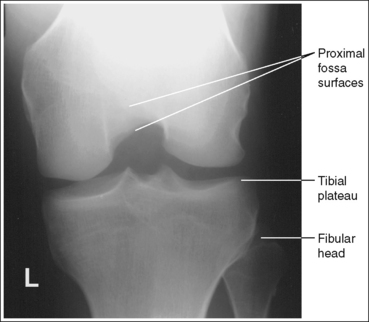

The knee demonstrates an AP projection. The medial and lateral femoral epicondyles are in profile, the femoral condyles are symmetrical, the intercondylar eminence is centered within the intercondylar fossa, and the tibia is superimposed over 0.25 inch (0.6 cm) of the fibular head.

• To obtain an AP knee projection, place the patient in a supine position with the knee fully extended. Internally rotate the leg until an imaginary line drawn between the medial and lateral femoral epicondyles is positioned parallel with the IR (Figure 6-71). This positioning places the medial and lateral femoral epicondyles at equal distances from the IR as well as medially and laterally in profile, respectively. It also centers the intercondylar eminence within the intercondylar fossa and draws the fibular neck and a portion of the fibular head from beneath the tibia.

• Effect of rotation. If the femoral epicondyles are not positioned parallel with the IR, an AP projection has not been obtained. If the patient's leg was not internally rotated enough to place the epicondyles at equal distances from the IR, they are not in profile, the medial femoral condyle appears larger than the lateral condyle, and the tibia is superimposed over more than 0.25 inch (0.6 cm) of the fibular head (see Image 54). If the patient's leg was internally rotated more than needed to place the femoral epicondyles at equal distances from the IR, the epicondyles are not demonstrated in profile, the lateral femoral condyle appears larger than the medial condyle, and the tibia is superimposed over less than 0.25 inch (0.6 cm) of the fibular head (see Image 55).

The knee joint space is open, the anterior and posterior condylar margins of the tibia are superimposed, the intercondylar eminence and tubercles are demonstrated in profile, and the fibular head is demonstrated approximately 0.5 inch (1.25 cm) distal to the tibial plateau.

• The anterior and posterior condylar margins of the tibia are superimposed if the correct central ray angulation, as determined by the patient's upper thigh and buttocks thickness, is used. By studying the tibial plateau region, you will see that the tibial plateau slopes distally approximately 5 degrees from the anterior condylar margin to the posterior condylar margin on both the medial and lateral aspects (Figure 6-72). Only if the central ray is aligned parallel with the tibial plateau slope is an open knee joint space obtained.

• Determining the central ray angulation. When a patient is placed in a supine position, the degree and direction of the central ray angulation required depend on the thickness of the patient's upper thigh and buttocks. This thickness determines how the lower leg and the tibial plateau align with the IR. Figure 6-73 shows a guideline that can be used to determine the central ray angulation for different body sizes; it illustrates the relationship of the tibial plateau to the imaging table as the patient's upper thigh thickness increases. Note that a decrease occurs in femoral decline, and a shift occurs in the direction of the tibial plateau slope as the thickness of the thigh decreases. Because of this plateau shift, the central ray angulation must also be adjusted to keep it parallel with the plateau and to achieve an open knee joint. For optimal AP knee projections, measure from the patient's anterior superior iliac spine (ASIS) to the imaging table on either side to determine the central ray angulation to use for each knee examination. When measuring this distance, do not include the patient's abdominal tissue. Keep the calipers situated laterally next to the ASIS. If the measurement is less than 18 cm, a 5-degree caudal angle should be used. If the measurement is 19 to 24 cm, a perpendicular beam should be used. If the measurement is greater than 24 cm, a 5-degree cephalad angle should be used. Using the correct central ray angulation not only results in an open knee joint space but also provides optimal demonstration of the intercondylar eminence and tubercles without foreshortening.

• Analysis of joint space narrowing. On an AP knee projection with adequate positioning, joint space narrowing is evaluated by measuring the medial and lateral aspects of the knee joint, which are also referred to as compartments. The measurement of each of these compartments is obtained by determining the distance between the most distal femoral condylar surface and the posterior condylar margin of the tibia on each side. Comparison of these measurements with each other, with measurements from previous images, or with measurements of the other knee determines joint space narrowing or a valgus or varus deformity. In a valgus deformity the lateral compartment is narrower than the medial compartment; in a varus deformity the medial compartment is narrower (see Images 56 and 57). Precise measurements of the compartments are necessary to ensure early detection of joint space narrowing and are best obtained when the knee joint space is completely open. If an inaccurate central ray angulation was used for an AP knee projection, the knee joint is narrowed or obscured, the intercondylar eminence and tubercles are foreshortened, and the tibial plateau is demonstrated.

• Center the central ray to the midline of the knee at a level 1 inch (2.5 cm) distal to the palpable medial epicondyle to place the knee joint in the center of the exposure field. (As long as the knee remains extended, an alternative central ray placement is 0.5 inch (1.25 cm) distal to the patellar apex.) Open the longitudinal collimation enough to include one fourth of the distal femur and proximal lower leg. Transverse collimation should be to within 0.5 inch (1.25 cm) of the knee skin line.

The femoral epicondyles are not in profile, the medial femoral condyle appears larger than the lateral condyle, and the fibular head demonstrates more than 0.25 inch (0.6 cm) of tibial superimposition. The leg was externally rotated.

Internally rotate the leg until the femoral epicondyles are at equal distances from the IR.

The femoral epicondyles are not in profile, the lateral femoral condyle appears larger than the medial condyle, and the fibular head demonstrates less than 0.25 inch (0.6 cm) of tibial superimposition. The leg was internally rotated.

Externally rotate the leg until the femoral epicondyles are at equal distances from the film.